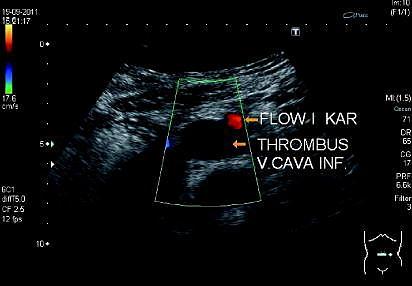

En 16-årig pige havde haft lændesmerter i en uge og blev indlagt. Ved indlæggelsen havde hun akut hævede ben med blålig misfarvning. Hun tog p-piller, røg ikke og havde et body mass index (BMI) på 37 kg/m 2 . Hendes tilstand i øvrigt var upåfaldende.

En a med Doppler viste dyb venøs trombose (DVT) i vena poplitea dexter et sinister, vena femoralis communis, vena iliaca communis og vena cava inferior op til vena renalis dexter-niveau.